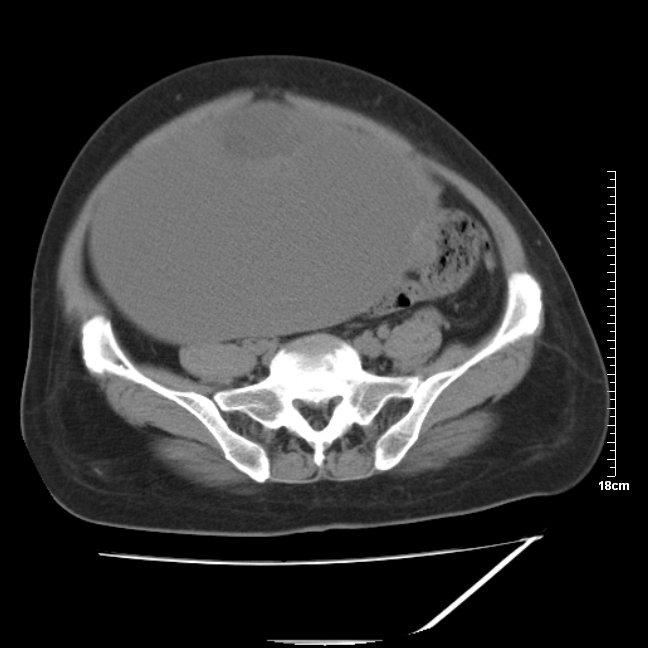

以下是引用jinning在2007-5-17 11:18:00的发言:[br]考虑右侧卵巢囊腺瘤合并少量出血可能性大